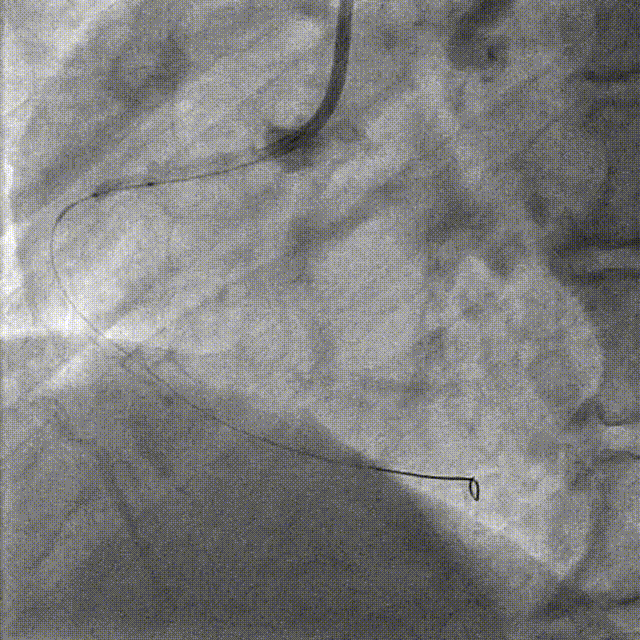

PCI-RCA TR, 7F JR4.0 ROTA with 2.0mm burr

Angiography post-ROTA